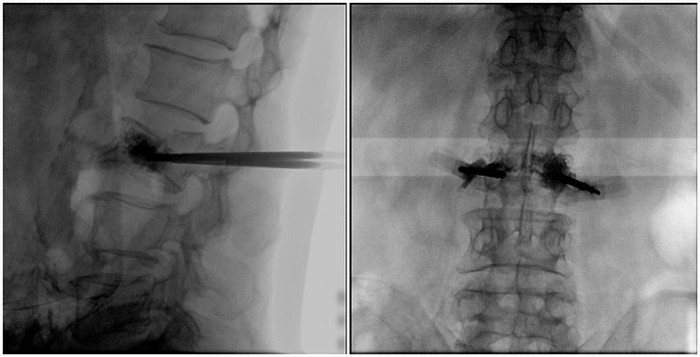

術(shù)中切口5毫米,在大平板C臂機(jī)的透視指引下,確定了進(jìn)針的方向及進(jìn)針的深度。經(jīng)椎弓根向椎體置管,建立通道,插入骨擴(kuò)張器(球囊)。球囊擴(kuò)張恢復(fù)椎體高度,并在椎體內(nèi)形成空腔,確定骨水泥的注入劑量,并注入骨水泥觀察其擴(kuò)散情況。

大平板C臂機(jī)臨床圖像